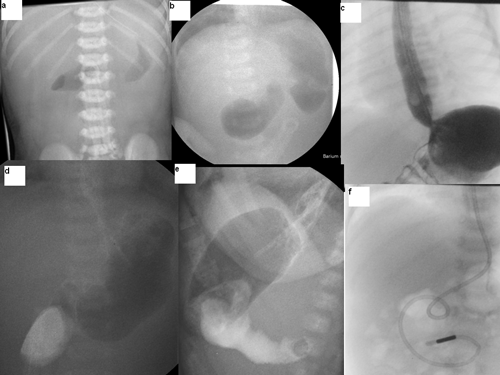

At exploration, there was no discontinuity of the duodenum externally and there was no visible or palpable rim of the attachment of the diaphragm externally. The first and second parts of duodenum were uniformly dilated and it was difficult to determine the exact site of the obstruction. A wide bore orogastric tube was passed into the stomach and pushed tenting at the windsock deformity. This led to demonstration of a faint indentation at the junction of the first and second part of duodenum.

A longitudinal incision centered on the indentation was made on the anterior duodenal wall and a complete mucosal duodenal diaphragm without any hole was identified. A distal windsock deformity was clearly evident (Fig. 2A and 2B).

Initially a small central hole was made; to see both sides of the diaphragm and the site of attachment to the duodenal wall especially to safeguard it from ampullary area in the diaphragm; followed by complete resection leaving a small thin rim close to the duodenal wall more on the medial side than the lateral aspect (Fig. 2C and 2D). The duodenal incision was closed transversely after advancing a jejunal feeding tube distally (Fig. 1f). Her post operative period was uneventful. Nasojejunal feeds were started on second postoperative day which were tolerated well. The gastro-oesophageal reflux was severe and she failed to gain weight initially and needed anti-reflux medications. She was discharged home on anti-reflux medications at 2 weeks of age. At 8-month follow-up, she was free of any reflux symptoms. The anti-reflux medications were stopped. She is now 15 months of age, asymptomatic and thriving well.

Figure 2: Intra-operative findings and steps. |